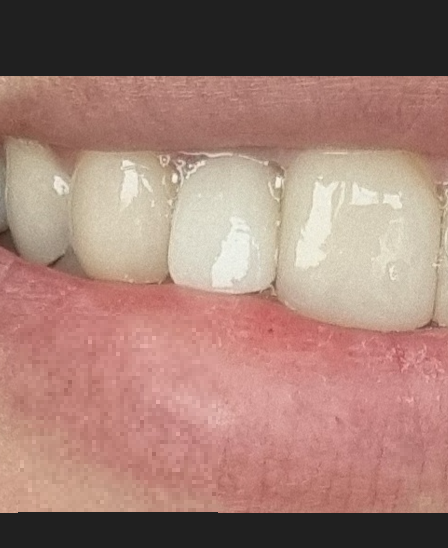

- 진료 결정 후 틀니 제작 준비 및 수술일까지 사용할 임시치아 요청 ( 임시치아는 언제든 빠질 수 있다고 하셨지만 여행 계획 때문에 꼭 필요하다고 요청드렸고, 다행히 수술 당일까지 잘 사용했지만 열흘동안 엄청 조심했어요)

2차 방문 (수술)

와 생각보다 진짜 너무 큰 수술이었습니다. 다들 임.플란.트를 시술 정도라고 하고, 광고에도 많이 나오니까 아무것도 아니겠지 했는데, 시간만 짧았지 너무 무섭고 힘든 과정이었습니다.